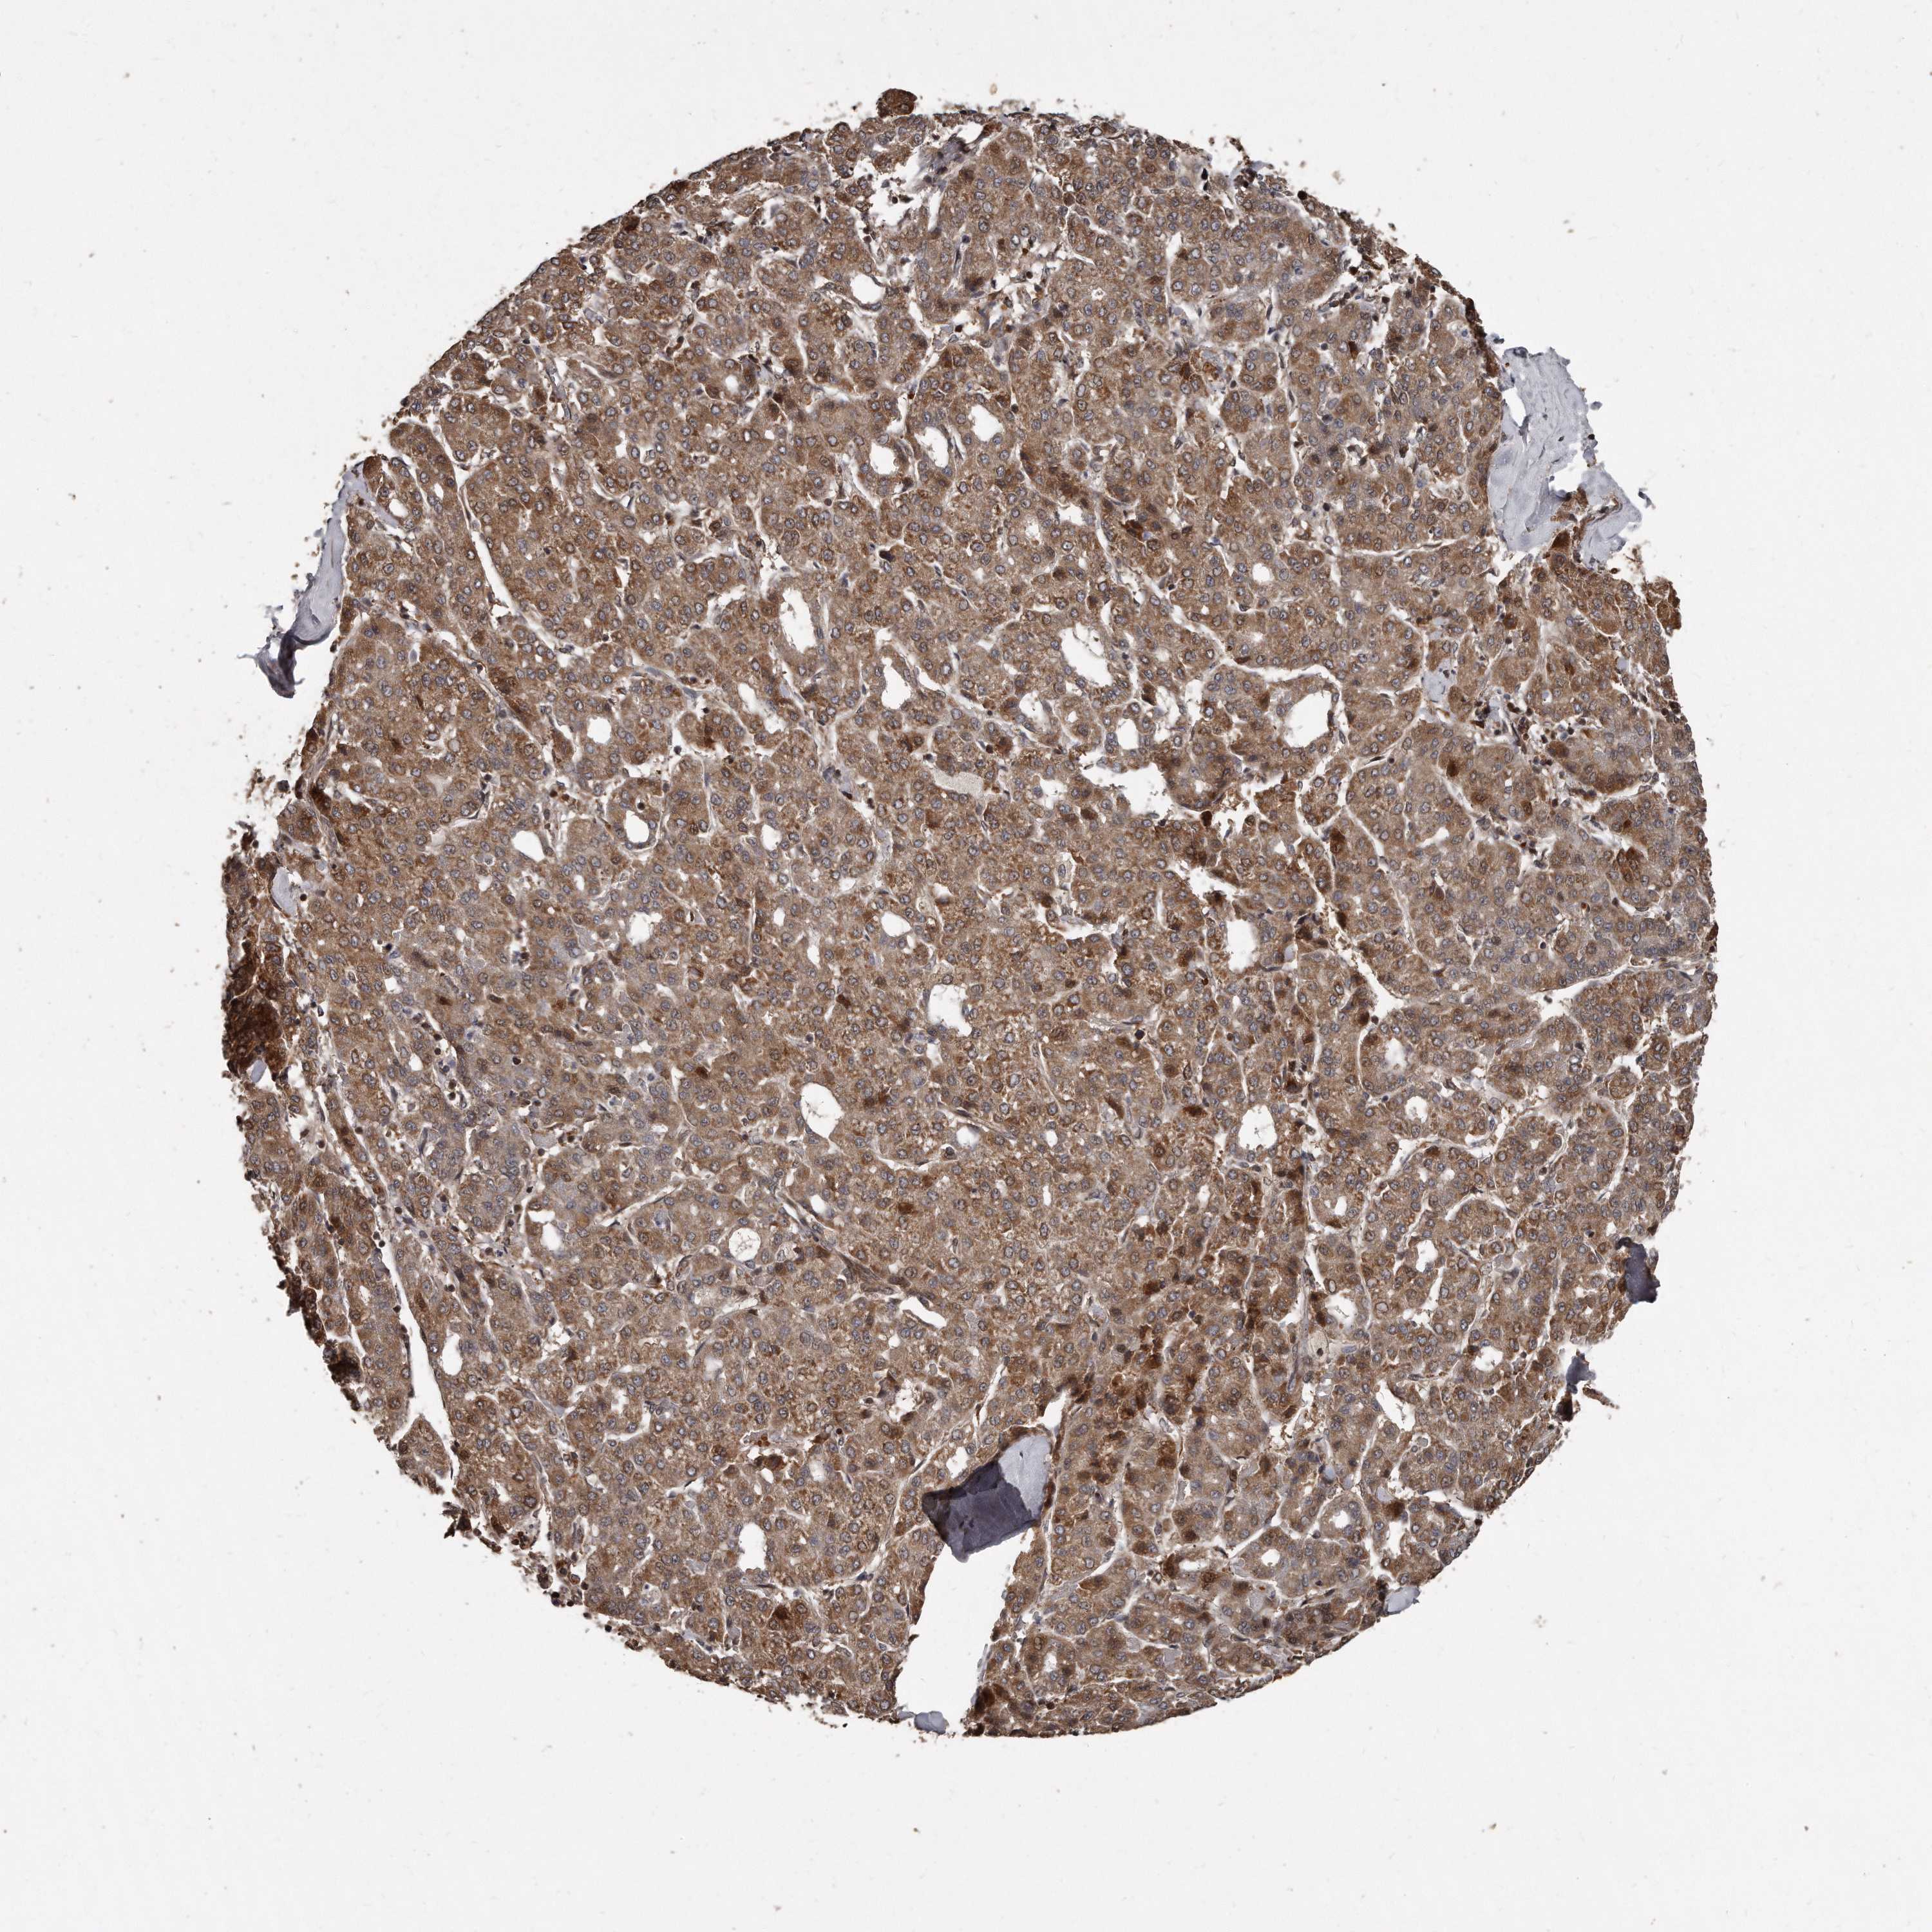

LIVER CANCER - Protein expressioni

A mouse-over function shows sample information and annotation data. Click on an image to view it in a full screen mode. Samples can be filtered based on level of antibody staining by selecting one or several of the following categories: high, medium, low and not detected. The assay and annotation is described here.

Note that samples used for immunohistochemistry by the Human Protein Atlas do not correspond to samples in the TCGA dataset.

Antibody stainingi

Antibody staining in the annotated cell types in the current human tissue is reported as not detected, low, medium, or high, based on conventional immunohistochemistry profiling in selected tissues. This score is based on the combination of the staining intensity and fraction of stained cells.

Each image is clickable and will lead to virtual microscopy that enables deeper exploration of all samples and also displays staining intensity scores, fraction scores and subcellular localization as well as patient and tissue information for each sample.

Antibody HPA028612

Staining

High

Medium

Low

Not detected

Intensity

Strong

Moderate

Weak

Negative

Quantity

>75%

75%-25%

<25%

None

Location

Nuclear

Cytoplasmic/membranous

Cytoplasmic/membranous,nuclear

Cholangiocarcinoma

Carcinoma, Hepatocellular, NOS